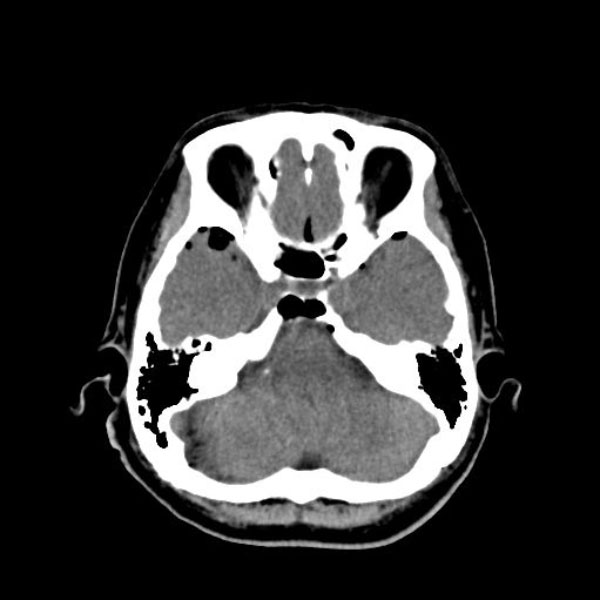

右顔面痙攣

術式